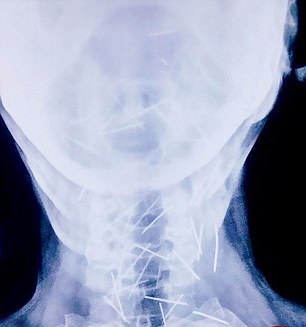

مردی هندی که برای انجام عمل جراحی‌ای ساده راهی بیمارستان شده بود پس از انجام رادیوگرافی، پزشکان متوجه وجود 75 سوزن در بدن این مرد شدند.

این مرد که «بادریلال مینا» نام دارد و در ایالت راجستان زندگی می‌کند برای عمل جراحی روی انگشت پایش به بیمارستان مراجعه کرد و پزشکان دریافتند سوزن های زیادی در پای او وجود دارد. بررسی‌های بیشتر نشان داد سوزن های دیگری نیز در بدن این مرد 56 ساله وجود دارد.

با اینکه این بیمار و خانواده‌اش از وجود این سوزن‌ها اظهار بی‌اطلاعی می‌کنند، به وضوح مشخص است آنها آگاهانه وارد بدنش شده‌اند.

تاکنون هیچکدام از بیمارستان‌هایی که این خانواده به آنها مراجعه کرده‌اند حاضر نشده‌اند برای خارج کردن این سوزن‌ها از بدن او کاری انجام دهند. از این 70 سوزن، 40 عدد از آنها در گلو، 25 عدد در پای راست و 2 عدد نیز در دو دست او است.